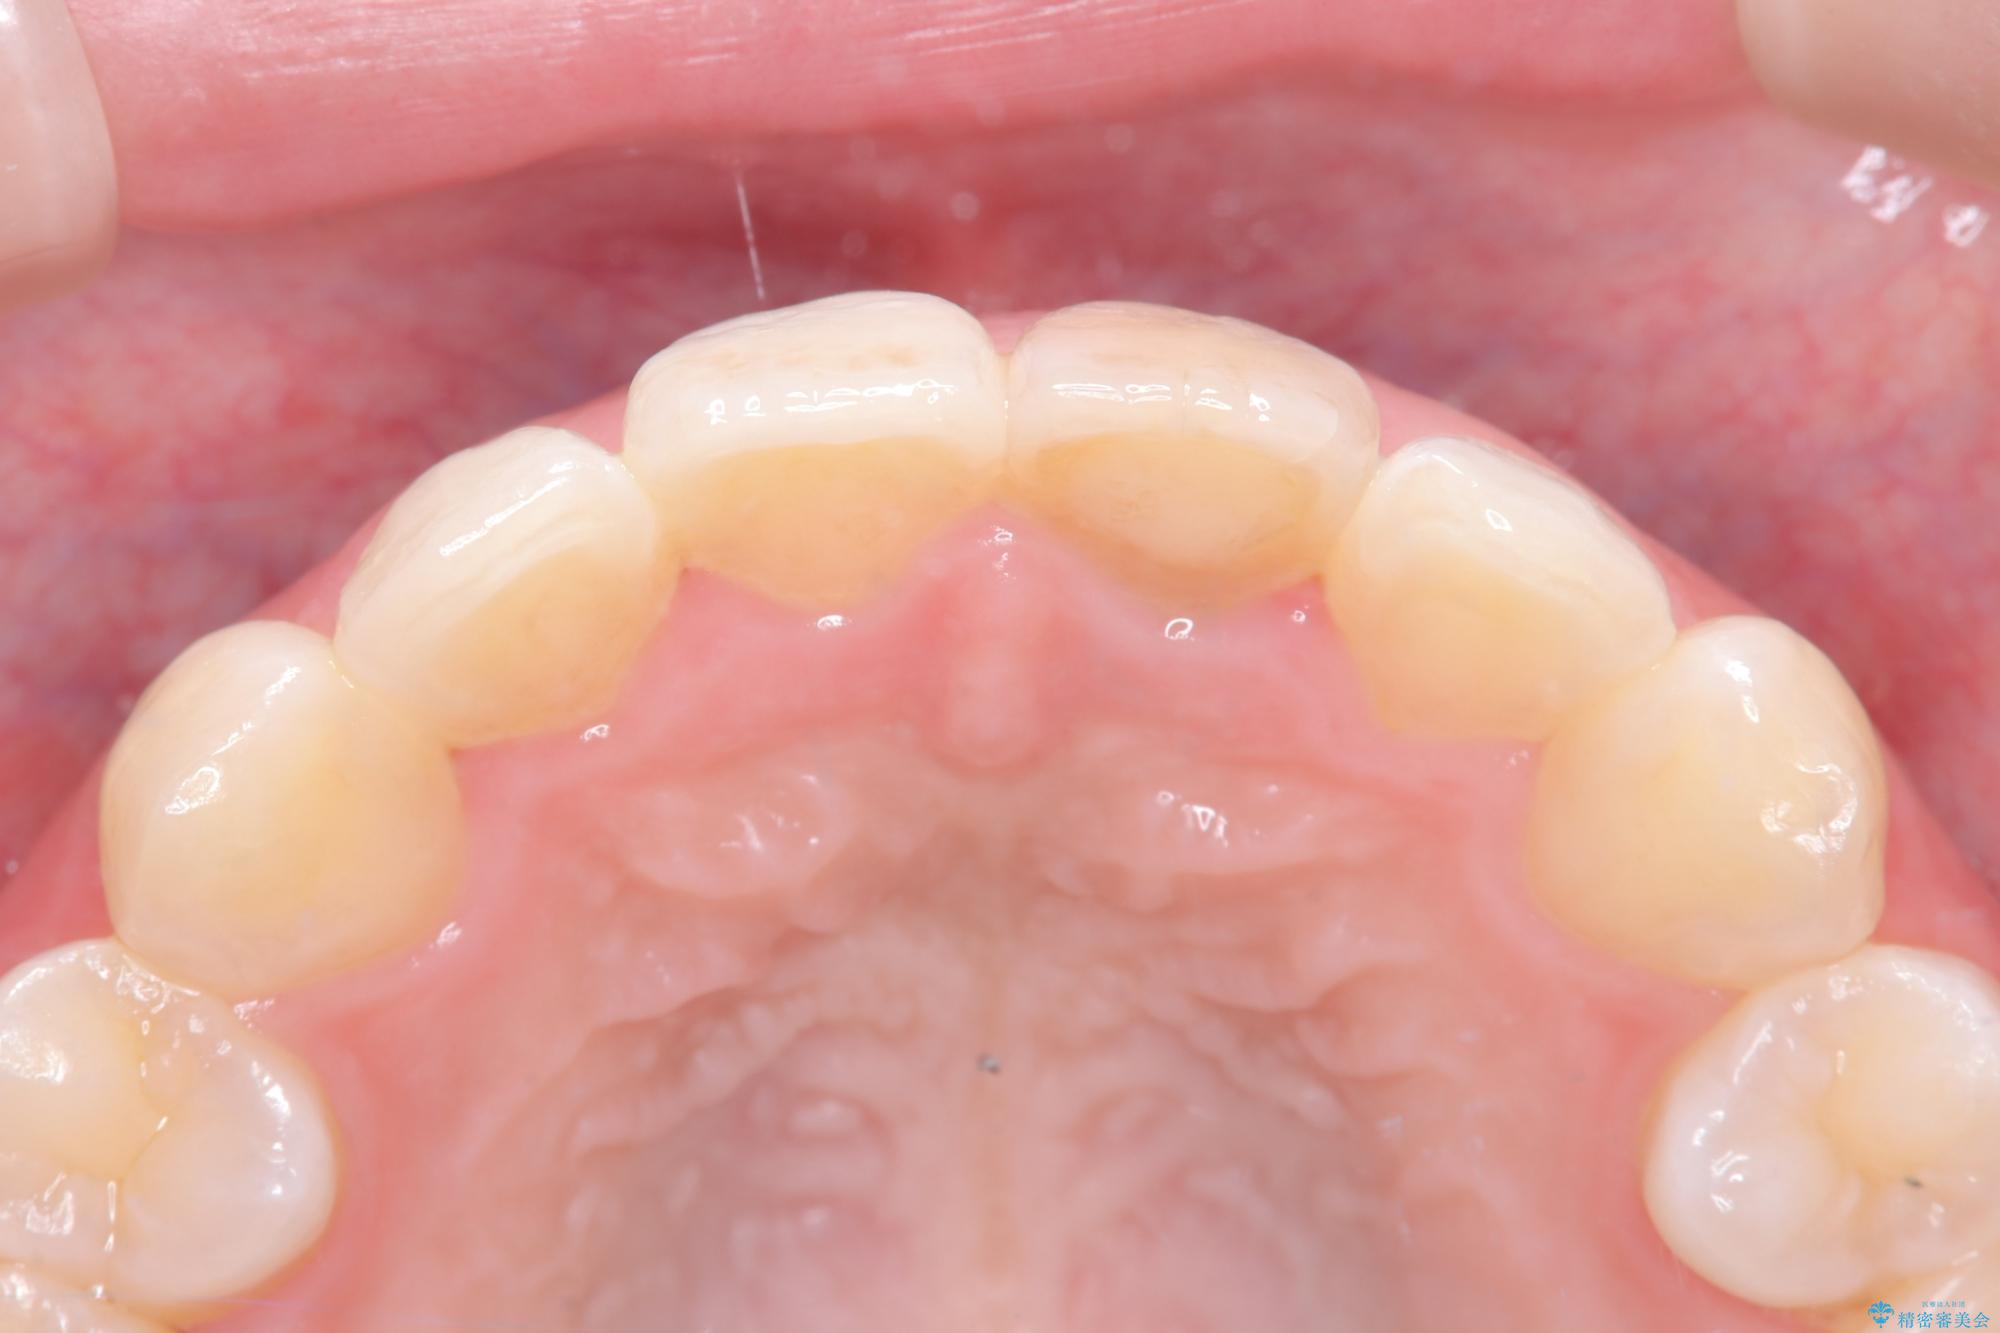

精密な再根管治療: 古い充填材を除去し、歯科用顕微鏡を用いて根管内を徹底的に清掃・殺菌しました。根の先まで確実に薬剤を詰め直すことで、将来的な根尖病変(根の先の膿)のリスクを最小限に抑えました。

オールセラミッククラウンによる修復: 最終的な被せ物には、一切の金属を使用しないオールセラミックを選択。隣の天然歯と色調や透明感を精密に合わせることで、どこを治療したかわからないほど自然な仕上がりとなりました。